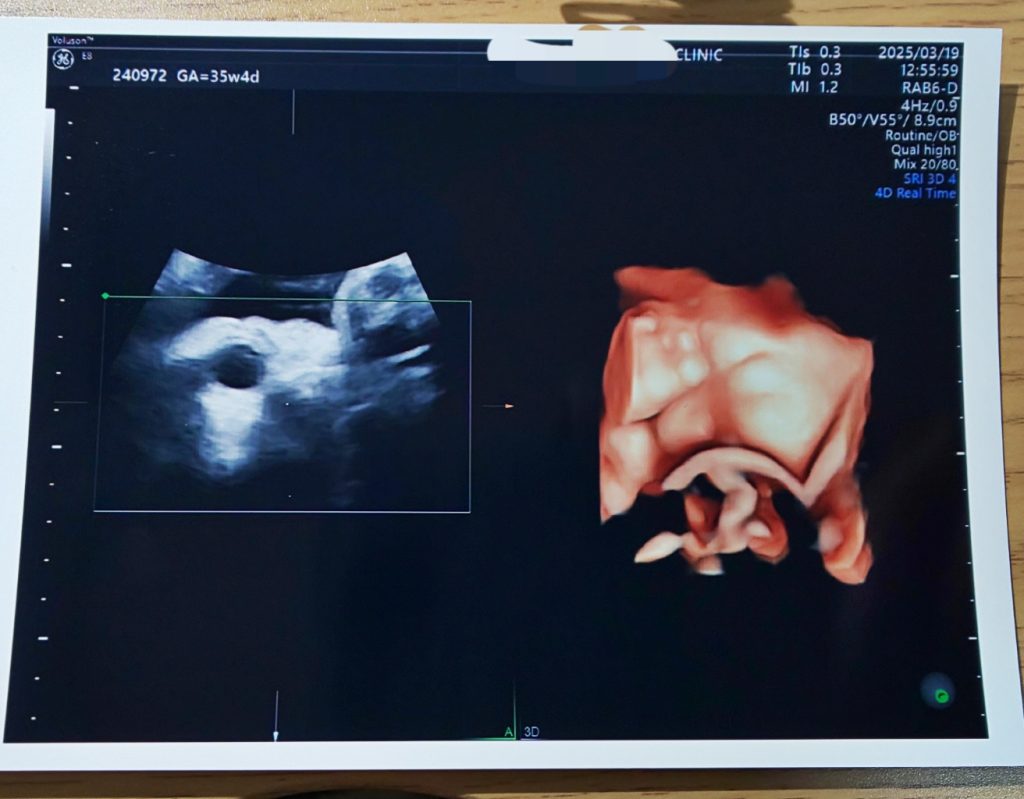

35週の健診はエコーのみ。今週末からいよいよ妊娠10ヶ月の臨月に突入!なので来週から出産まで週1の妊婦健診になります。以下、エコー写真と中の人のお腹載せてるので閲覧注意です~

エコーでこちゃの様子を見てもらいましたが、またちゃんと顔を見せてもらえず…。頭の位置は下がってきているようです。先生が撮ってくれたこのエコー、眉間に皺をせて目をぎゅっとつむっていて鼻も見えているんですが、右目の部分を手?で隠してるんですよね…

妊娠後期の赤ちゃんは頭を下にして、体を丸くする体勢になるんだけど、この子は体が柔らかいのか脚を伸ばしているのか頭の部分に足がきてます

先生がエコーを当てていた頭のある場所は最近胎動が凄すぎて痛むぐらいだったんですが、頭と手と足があるからボコボコお腹が変形するぐらいの胎動なのは当たり前のことでした。こちゃどんな体勢してんの…。そして胃付近に浮き上がってくる頭みたいに丸くてでっかい塊が実はお尻ということも判明。私のお腹の右下に頭、左上にお尻があるそうです。胃付近に浮き出てくるのがあまりにもまん丸な形だから逆子なんじゃないかと心配した…

こちゃの推定体重は2500gで平均ど真ん中。恐らくお産の時には3000gを越える予測だそうです。1週間後の健診では内診と採血。ウォーキングと安産体操サボってると内診でバレるのでそろそろウォーキング再開します…雪降ったり風が強かったりで家に引きこもってました…